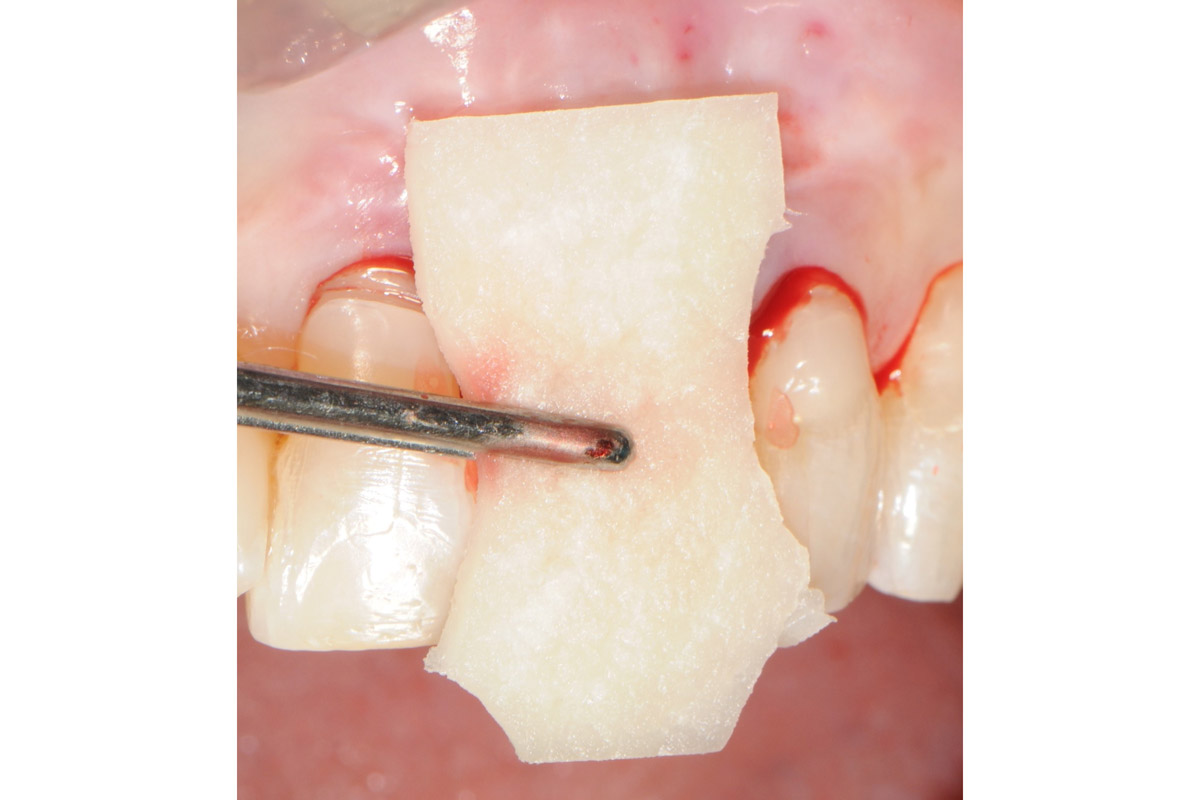

7/18 - Hydration of mucoderm® for a few minutesTooth extraction and socket sealing with mucoderm® - Dr. A. Rossi

8/18 - Application of mucoderm® that is cut into shapeTooth extraction and socket sealing with mucoderm® - Dr. A. Rossi